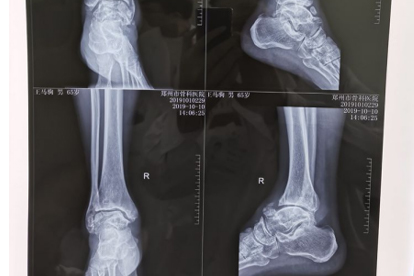

三、腳部疼痛或麻木

1、持續性疼痛:可能是關節炎、痛風或神經病變的徵兆,尤其是夜間加重的疼痛。